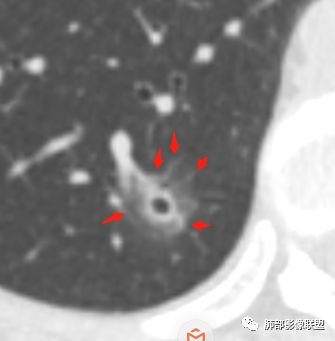

晨读:52f,体检发现右下肺结节,空洞、周围晕征(磨玻璃),局部血管影增粗,考虑1.真菌感染;2.GPA或不典型单发转移待排。

右下肺混合磨玻璃结节,其内见空洞,空洞壁光滑,结节周围可见晕征,可见增粗血管,首次体检发现患者无症状,还是建议抗炎2周,1个月后复查,鉴别腺癌。

横断位看上去晕很模糊,冠矢状位重建后却比较清晰,所以单次CT检查蛮难定的,中心透亮区一定是空洞吗?我怎么觉得是一支气管壁有增厚,管腔有轻度扩张的支气管,第一感觉还是炎性结节吧,PC可能大,一定要否定腺癌也不敢,一个月左右复查。

体检发现肺部结节,右下肺混合密度结节,结节中心空泡,壁光滑,结节边缘模糊,血管在结节内增粗,矢状位前基底段还有一片磨玻璃影,所以考虑良性结节可能,炎性肉芽肿?抗炎后复查。腺癌合并炎性改变待排。

晨读病例,右肺下叶小结节病灶,内可见光滑空洞,周围可见边缘模糊磨玻璃影,首先考虑感染性病变,真菌或结核可能,鉴别腺癌,后者小病灶空洞少见,周围磨玻璃影清晰,胸膜凹陷征。

mGGO,周围有晕,边界不清,空洞,收缩力不强,血管通过走形正常,首先考虑炎性结节,抗炎和复查。筛查真菌。

内部低密度是空洞还是扩张的细支气管有疑问,边缘有的层面清楚有的层面模糊,恶性待排吧。

我未见过的类型,CT征像良恶参半。女性,52岁,腺癌的好发人群。良性征像外周纯磨玻璃影很大,而且境界欠清晰。恶性征像,中央薄壁气囊边缘实性增厚,而而且厚薄不均匀。结合性别年龄,腺癌首先考虑,处理:随访3-6月,看看实性部分有无增多,应该不影响生存率。

磨玻璃结节,中央有空洞,周围晕征,磨玻璃血运明显,考虑腺癌,鉴别隐球菌。

晨读:结节伴晕,晕模糊,内有小空洞,周边还有片状模糊影,支持首先考虑炎性,临床会先抗感染治疗后复查。

晨读:右下肺结节,结节中心小空洞,壁光滑,结节周围有晕,边缘模糊,其他基底段亦可见斑片磨玻璃影,考虑炎性肉芽肿。隐球?寄生虫?

晨读:中老年女性,体检来诊。右肺下叶后基底段近胸膜下mGGN,其内实性成分似见毛刺及分叶,并见空泡征,周围GGO边界清楚,近肺门端见血管影伸入病灶并略显扩张,病变与支气管关系观察欠佳。多考虑恶性,腺癌可能性大。鉴于首次检查,常规建议抗炎治疗后复查,观察病灶变化情况,再决定下一步诊疗方向。

晨读,中老年女性,右下肺混合磨玻璃结节,边界模糊,内有空泡,张力高,考虑支气管扩张,周围血管相连,稍有增粗,考虑良性病变,细支气管扩张畸形并周围炎。腺癌待排。

晨读,女,52岁体检发现结节,右肺下叶见磨玻璃样结节影,边缘见毛刺,病灶内可见小空泡影,考虑腺癌可能,待除外炎性病变。

病灶内低密度像扩张的支气管,整体被病灶包围,可以定为空泡,PC没有这么大的牵拉,曲霉的话病变范围太小,而且是体检发现。病灶周围磨玻璃似清非清,病灶下缘磨玻璃是明确清晰的,因此诊断倾向于粘液腺癌,比较心虚的地方是没有抗炎复查。

右肺下叶后基底段混合型磨玻璃结节,边缘见晕征,内见小空泡/空洞,其内壁光整,与支气管关系不密切,常规考虑炎性肉芽肿病变,结核/隐球菌可能,腺癌待排,建议抗炎1月后复查。

右下叶后基底段混合密度结节,边缘磨玻璃模糊,晕征,中心实性成分似有多个小结节融合,收缩力不明显,中心空泡样改变内缘光滑,考虑小空洞,综合考虑良性炎性结节,隐球可能,结核与曲霉待鉴别。抗炎后复查或穿刺活检。

右肺下叶混合磨玻璃结节,中心有小透光区,壁光整,磨玻璃边缘模糊,收缩力不明显,考虑炎性结节,抗炎治疗后复查,代排隐球菌。

右肺下叶基底段胸膜下小结节,周围模糊晕征,其内光滑囊腔影,考虑小空洞,其内血管走形自然,周围软毛刺,常规考虑炎性结节,隐球可能性大,建议抗感染后复查,鉴别粘液腺癌。

从那么多天以来的读片结果看,不要走寻常路,各位老师考虑炎性的多,小隐球结节还是实性的多(见得少不知道对不对),空洞张力较高,那我考虑腺癌。